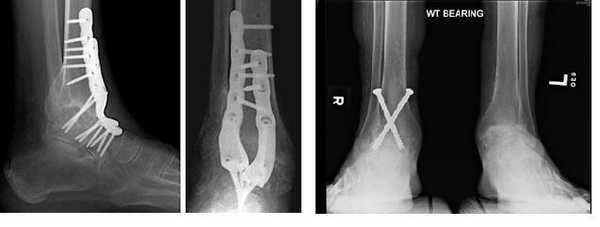

Большеберцово-таранный артродез.

Больше подходит для пожилых малоактивных пациентов, так как сильно нарушает биомеханику ходьбы. Позволяет значительно снизить болевую симптоматику за счёт полного исключения движений в повреждённом суставе. Артродез может быть выполнен с использованием множества различных фиксаторов и методик в зависимости от предпочтений и возможностей оперирующего хирурга. Приводит к быстрому развитию артроза в подтаранном суставе (50% через 10 лет).

Артропластика голеностопного сустава.

Эндопротезирование голеностопа – передовое направление в лечении артроза голеностопного сустава. Для эндопротезирования голеностопа есть много ограничений и противопоказаний: выраженная деформация, выраженный остеопороз, остеонекроз таранной кости, стопа Шарко, выраженная нестабильность голеностопного сустава, ожирение, выраженные нейро-трофические изменения. Современные модели протезов позволяют минимизировать резекцию костной ткани, сохраняют точки прикрепления мышц. За последние 10 лет собраны статистические данные, указывающие на высокую удовлетворённость пациентов, 70-90% хороших и отличных клинических результатаов при соблюдении условий правильного подбора пациентов и техники операций.